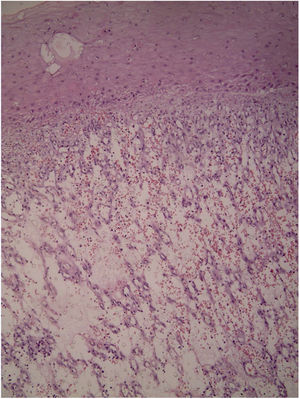

Case reportA 45-year-old man with ankylosing spondylitis had been treated with adalimumab for five years. He reported an erythematous papule on the right forearm for four months, evolving with vegetative growth, fast-growing, friable, red-colored, measuring about 4.5cm in diameter (Figs. 1 and 2). He reported pain and episodes of spontaneous bleeding. The lesion was excised and the histopathological examination showed an ulcerated nodule. In the superficial dermis, there was a proliferation of small vessels and intense inflammatory infiltrate of neutrophils with fibrin deposition. In addition, foreign body giant cells phagocytosing refractory exogenous material were reported. In the deep dermis there was a proliferation of dilated capillaries in the midst of a plasmacytic and histiocytic inflammatory infiltrate, compatible with lobular capillary hemangioma (Figs. 3 and 4). The patient maintains the use of adalimumab without the appearance of new lesions.